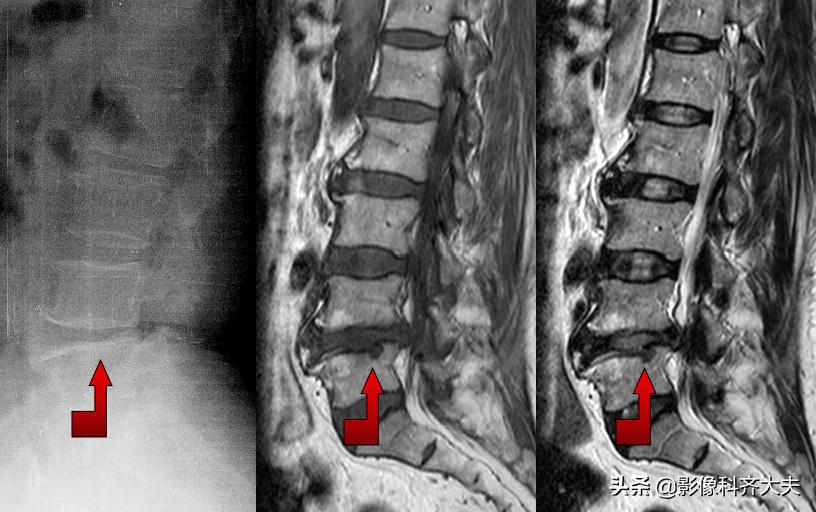

正侧位示腰4、5间隙变窄,CT扫描示腰4、5间盘突出

MRI:腰 5-骶1间盘脱出

MRI:腰椎间盘脱出